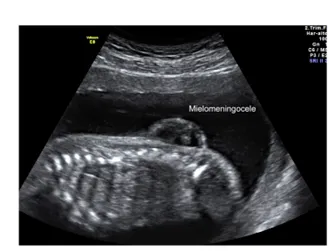

Espina Bífida

Imagen ecográfica correspondiente a  un mielomeningocele. Se evidencia la masa que contiene en su interior los nervios de la médula espinal.

Las características de la ecografía que sugieren una espina bífida incluyen una masa quística en cualquier lugar de la columna. Cuando se trata de un mielocele se evidencia el defecto óseo sin la presencia del saco.